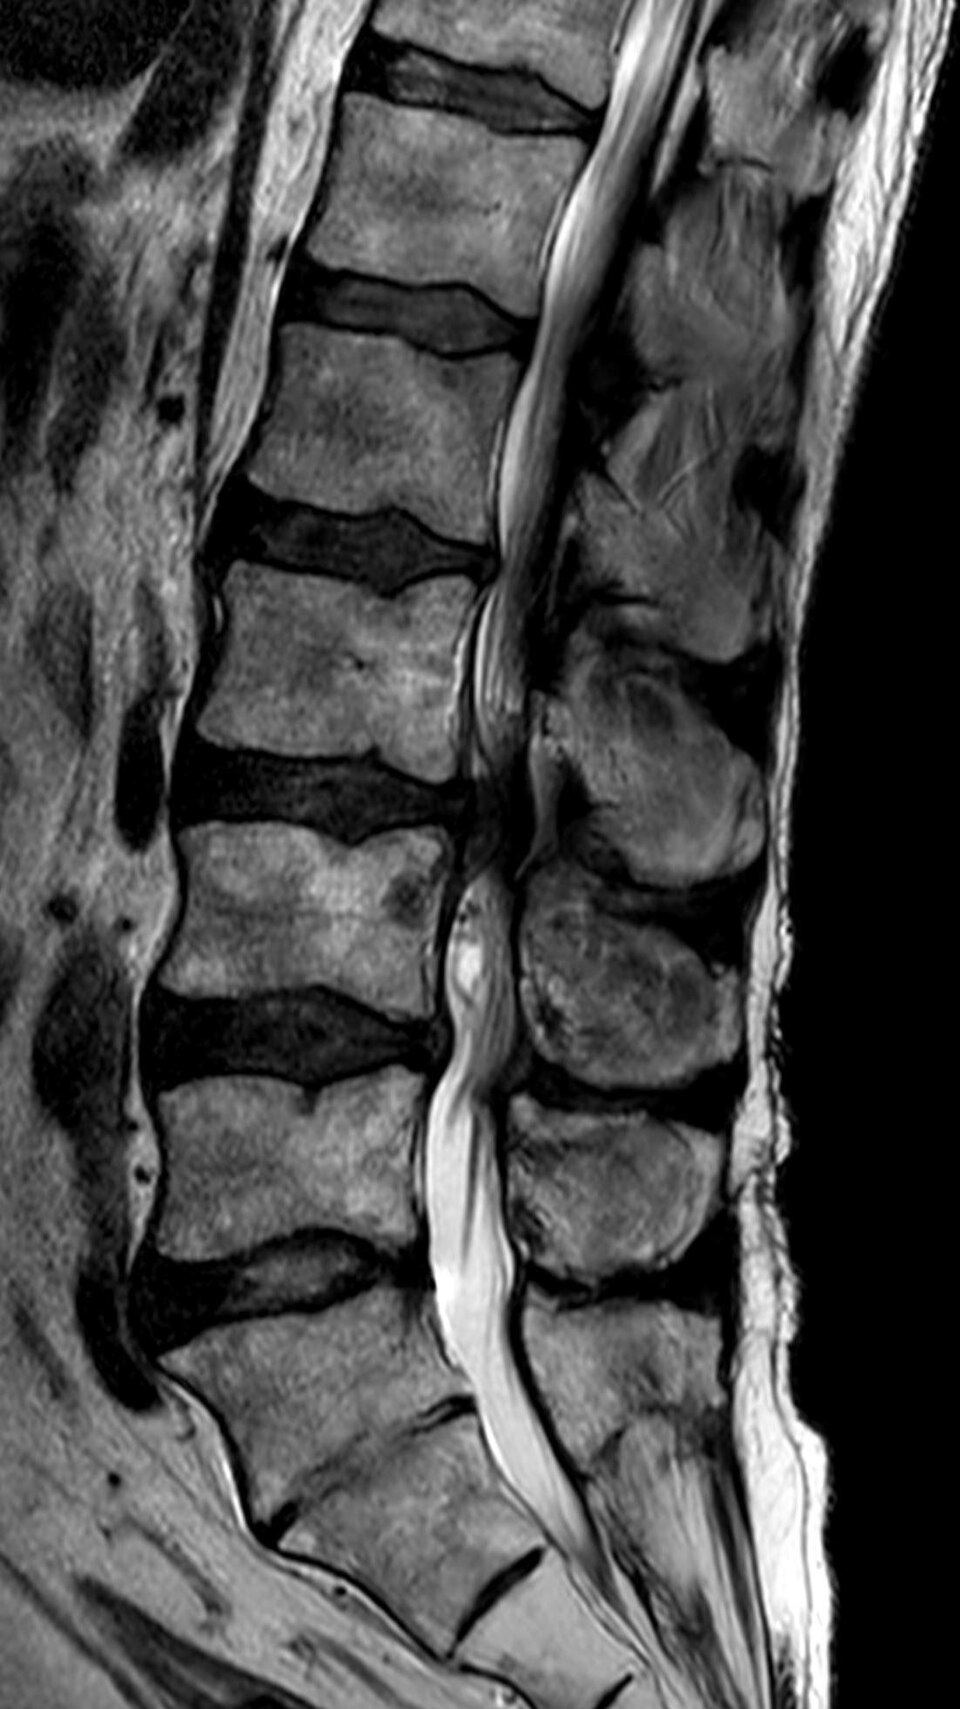

Normal lumbar spine phantom with healthy vertebral bodies, intact discs, spinal canal, and nerve roots

L4-L5 posterolateral disc herniation compressing the L5 nerve root with disc desiccation, annular tear, and...

Lumbar spinal stenosis with ligamentum flavum hypertrophy, facet joint arthropathy, disc bulge, and narrowed central canal